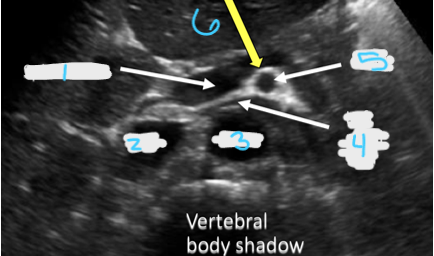

<p>In this transverse view, what is #1?</p>

In this transverse view, what is #1?

Portal Vein

<p>In this transverse view, what is #2?</p>

In this transverse view, what is #2?

IVC

<p>In this transverse view, what is #3?</p>

In this transverse view, what is #3?

Aorta

<p>In this transverse view, what is #4?</p>

In this transverse view, what is #4?

Left Renal Vein

<p>In this transverse view, what is #5?</p>

In this transverse view, what is #5?

SMA

<p>In this transverse view, what is #6?</p>

In this transverse view, what is #6?

Splenic vein